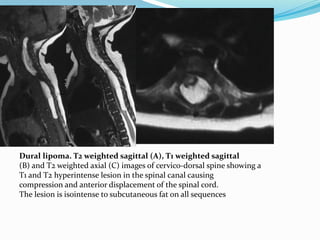

Dural lipoma. T2 weighted sagittal (A), T1 weighted sagittal

(B) and T2 weighted axial (C) images of cervico-dorsal spine showing a

T1 and T2 hyperintense lesion in the spinal canal causing

compression and anterior displacement of the spinal cord.

The lesion is isointense to subcutaneous fat on all sequences

 Intradural lipoma; It is a midline lipoma in the

groove of unopposed neural placode in its dorsal

surface within an intact dural sac

 The intact dura help to differentiate this from

lipomyelocele and lipomyelomeningocele .usually seen

in lumbosacral region and are associated with tethered

cord syndrome